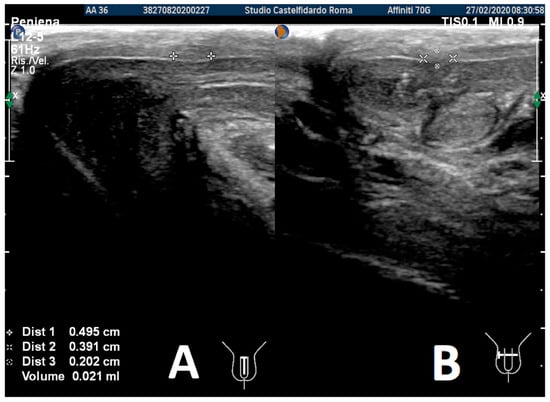

After the third treatment cycle, the patient underwent a similar follow-up with a physical exam and a penile Doppler ultrasound. The IIEF score was 27. We then observed a dorsal penile curvature of 15 degrees (unchanged). The penile ultrasound showed the following plaque dimensions: 4.95 × 3.91 × 2.02 mm (21 mm3 = volume) (Figure 12).

Compared to its initial measurement, the plaque had therefore undergone a 97% reduction in volume.

Figure 12. Ultrasonography of the penis after the 3rd therapy cycle. (A) Longitudinal view; (B) axial view.